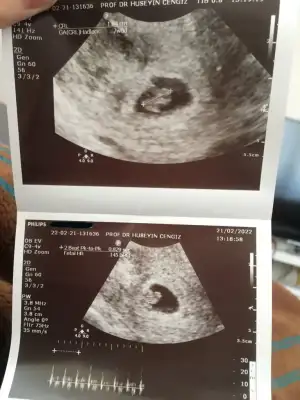

Sabah rahimde hafif kramp oluyordu ara ara dedim düşecek herhalde 0 umutla gitmiştim doktora.

Doktorum hemen vajinal kontrol yaptı kaşıkla rahim ağzına baktı herhangi bi açılma olmaması bizi mutlu etti. Kanamam çamur rengine döndü azaldı ama devam ediyor.

Bebeğimin kalbini duyduk, en son 2 gün önce cumartesi kontrolde 0.81 mm idi, şimdi 1.04 cm çıktı gelişimi devam etmiş. Kese büyüklüğü gayet iyi dediKalbi de 145 ile atıyor. Ultrasonda 7+0 çıktı, bugün 7+2 aslında ama sorun yok. Kalp atışının ileriki günlerde artması bekleniyormuş.

Kanama alanı var neredeyse kese alanı kadar 2 cm büyüklüğünde. Düşük riskimin mevcut olduğunu, tam yatış yapmamı söyledi. Progestan, proluton ve coraspirine devam ediyorum zaten. 10. Ve 12. Haftaları bekleyeceğiz kanaman devam edecek leke şeklinde olması güzel, o kanama alanı akarak bitecek dedi. Geçmişte rahim içi operasyon geçirmiş olmam filan tetikliyormuş. Lekelenmenin de 1 hafta- 10 güne filan bitmesini bekliyoruz inşallah tamamen.

Eğer sağlıklı bir gebelik ise düşmez ama değilse elimizden hiçbir şey gelmez düşer 10. Haftadan sonra dedi. hepimizin bildiği bir şey bu zaten. Şimdi kritik şekilde bekliyoruz, bebeğin gelişiminin devam etmesi ve iyi olması, kanamanın azalması ve kırmızıdan çamura dönmesi, kramplar ve kötü sancıların olmaması gibi seyler Umut verici. Tuvalete ve yemek yemeye kalkmak serbest sadece. Annem gelecek yardıma o sebeple.

Doktorumun dediğine göre araştırmalar da bunu gösteriyor diyor 12-14 hafta atlatıldıktan sonra %95 ihtimalle biz annemizin kucağına bebeği verdik gözüyle bakıyoruz dedi. Doğum paketi yaptıracaktık ama beklemeye aldık henüz. 10 ya da 14 gün sonraya bi randevu alıp bakacağız duruma göre. İlle evinin yakınında seni takip eden, benimseyen bi doktor olsun diyor.

Durumlar böyle dün akşamdan beri perişan olduk eşimle ama çok şükür umudumuz yeniden yeşerdi.